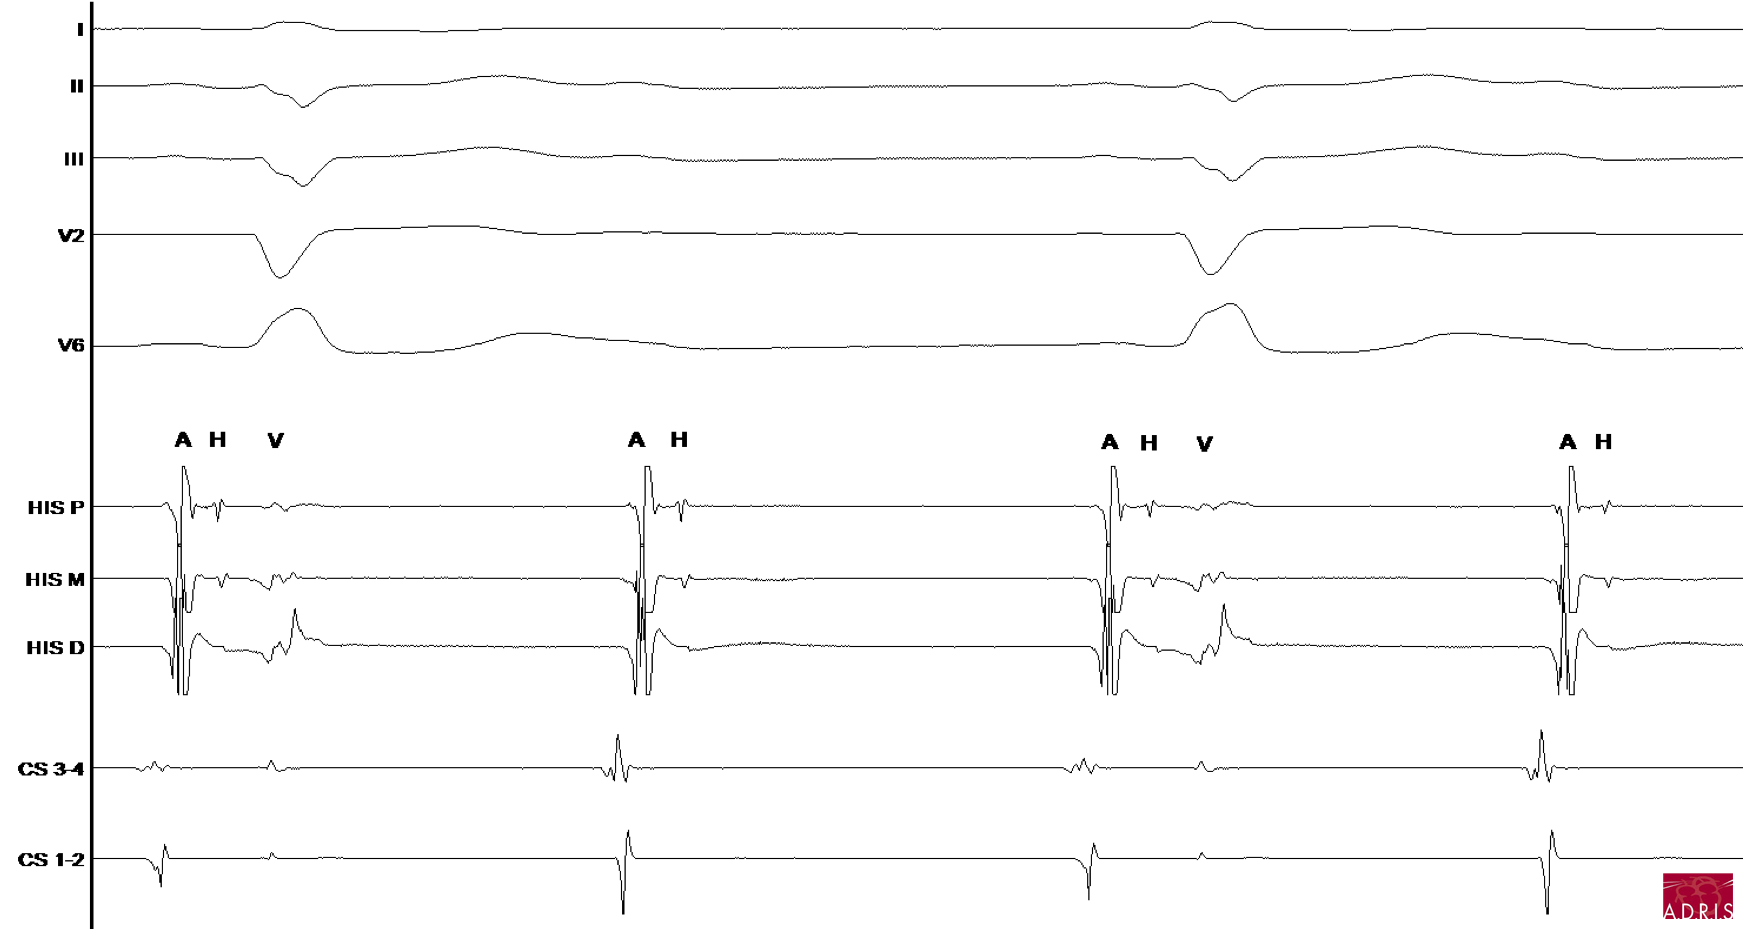

Cas clinique 1 : BAV 2/1 infra-nodal

ECG

Endocavitaire